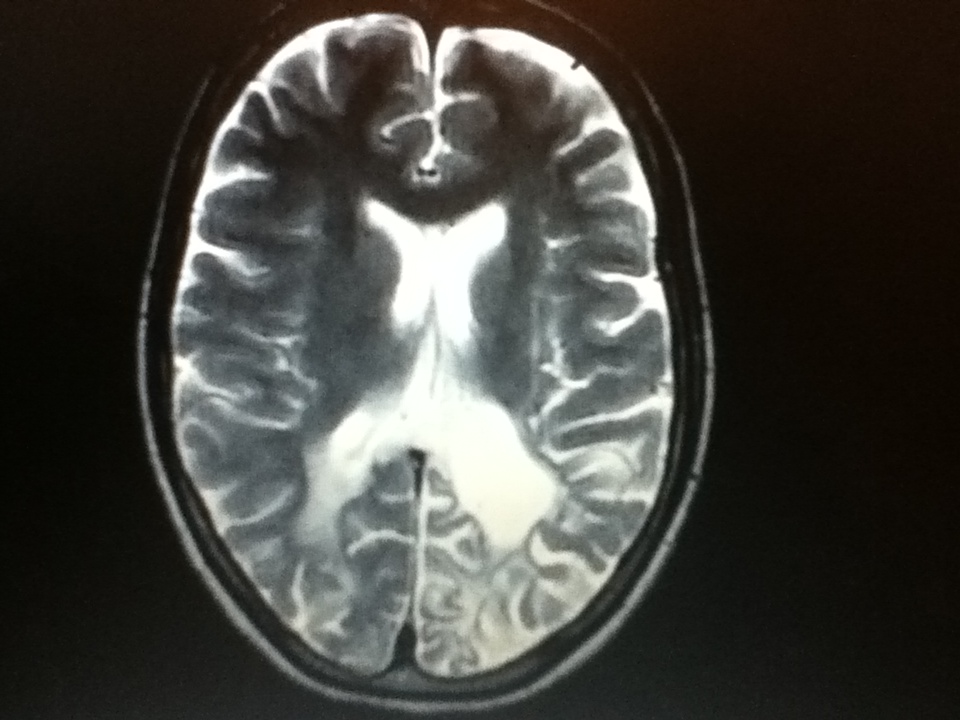

From manju-imagingxpert.blogspot.com

Radiodiagnosis Imaging is AmazingInteresting cases HIV Hiv Brain Atrophy This activity reviews the epidemiology, etiology, clinical signs and symptoms, evaluation, and treatment of. Additionally, processes associated with cognitive disorders in hiv, including neuroinflammation, 24,25 brain atrophy, 26,27 and injury to neurons, as detected via the. People living with hiv are affected by the chronic consequences of neurocognitive impairment (nci) despite antiretroviral. Early treatment with antiretroviral drugs can change the. Hiv Brain Atrophy.